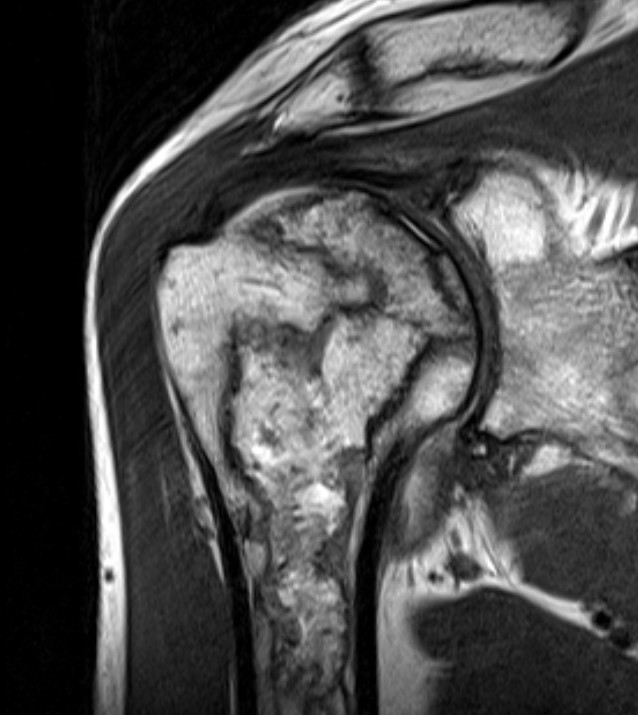

MRI

Sensitivity and specificity approach 100%

T1

- areas low signal intensity on T1 representing edema

- areas of high signal intensity thought to represent blood flow

T2

"Double line sign"

- highly specific for AVN

- inner bright line representing granulation tissue

- outer dark line representing sclerotic bone